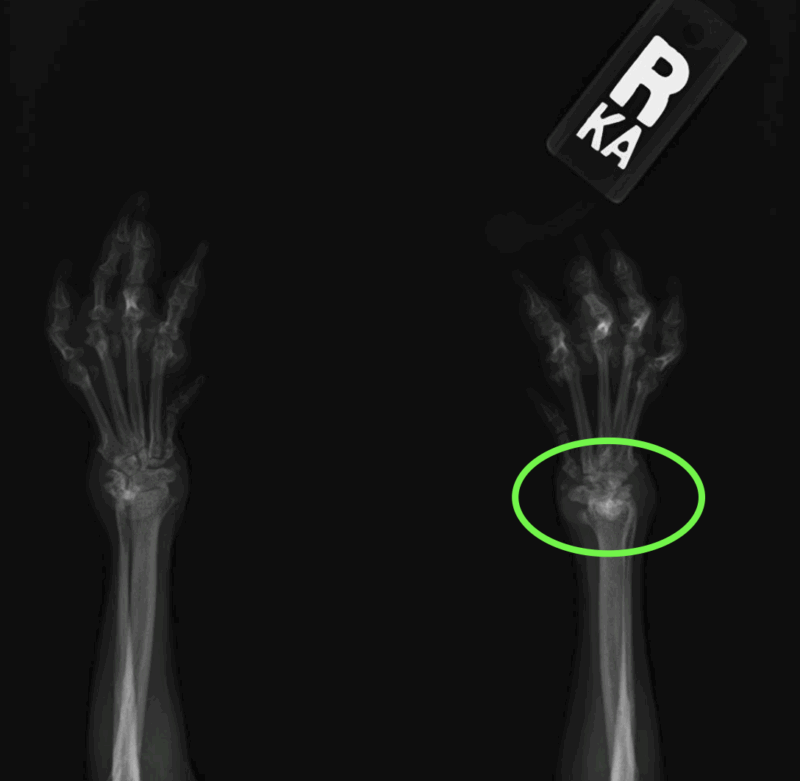

7歳の未避妊雌のチワワが右前肢を挙げていて、関節が変形しているという主訴で来院しました。

触診・視診では両前肢の手根部に変形が認められ、慢性的な関節疾患が疑われました。

両前肢の手根関節の変形が見られるのが分かります。

レントゲン検査では右前肢の手根関節脱臼を確認し、臨床所見と合わせて関節リウマチが強く疑われました。

この症例ではステロイドと免疫抑制剤であるシクロスポリンの内服を開始すると同時に、関節の安定性を高める目的でサポーターを装着しました。